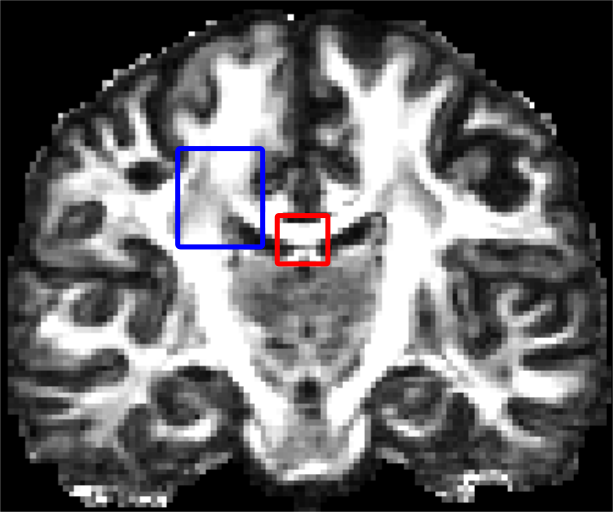

Non-negative spherical deconvolution (NNSD) (Cheng et al., 2014) is performed to estimate non-negative fiber ODFs from three-shell DWI data. NNSD works for multi-shell data. It is more robust to noise, and the obtained fiber ODFs (fODFs) in isotropic regions are closer to the isotropic spherical PDF, compared with conventional constrained spherical deconvolution (Tournier et al., 2007). After obtaining the fODFs by NNSD, the peaks are detected from the estimated fODFs with GFA larger than , as described in Section 3.4. OO and OD are calculated from the spherical harmonic representation of fODFs along their principal peaks as shown in Algorithm 1. The second row in Fig. 11 demonstrates FA from tensors estimated by DTI, OO and OD from fODFs estimated by NNSD, and the total distortion map estimated from the local orthogonal frames of fODFs. Fig. 12 and 13 show the close-up views of fODFs, local orthogonal frames, and the six proposed indices for the red and blue regions in Fig. 11, where the region shown in 12 is also visualized in the DFA pipeline in Fig. 1. The fODF glyphs are colored by using its sampled directions. The three orientations in the local orthogonal frame in each voxel are visualized by using three tubes in red, green, and blue colors respectively. There is no local orthogonal frame in some voxels because those voxels have GFA values lower than . These figures show the following: 1) OO is high in anisotropic areas with well-aligned directions, while OD is high in isotropic or crossing areas. 2) The four orientational distortion indices are low in areas with well aligned principal directions, and zero in isotropic voxels without peaks. Distortion indices are high in voxels where the principal directions in its local neighborhood change largely. 3) The central voxels in red region is the crossing area of the Corpus Callosum from left to right and Fornix that goes through the coronal slice. The twist index showed high value in this crossing area as expected.

OO and OD by NODDI are different from OO and OD by NNSD in Fig. 11. We propose OO and OD as general properties (i.e., the degree of aligment and dispersion along peaks) for general ODFs, like GFA for ODFs, independent of diffusion signal models. OO and OD can be calculated from ODFs estimated by the NODDI model (Zhang et al., 2012), the tensor model in DTI (Basser et al., 1994), and various spherical deconvolution methods (Tournier et al., 2007; Cheng et al., 2014), etc. In this sense, we claim that the proposed OD (and OO) inspired from liquid crystals is more general than the dispersion index in NODDI that only works for Watson distributions.